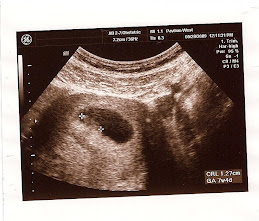

Sooo, here we are...almost done with week 26! Can't believe that we will soon culminate our 2nd trimester! So weird! Last week was our most recent doctors appt. So far my total weight gain is 9 lbs, I've grown 4 cm (bringing my uterus to 25 cm), and things are progressing beautifully. Thankfully, all my weight gain has been right in the belly area and I am feeling great (let's keep that going for at least another few weeks :)). The baby is moving sooo much lately and if I lay still enough, you can actually see my belly move around! It is the neatest yet weirdest thing! Oct 21st will be my last monthly visit to the OB, then I will go every other week, then weekly!